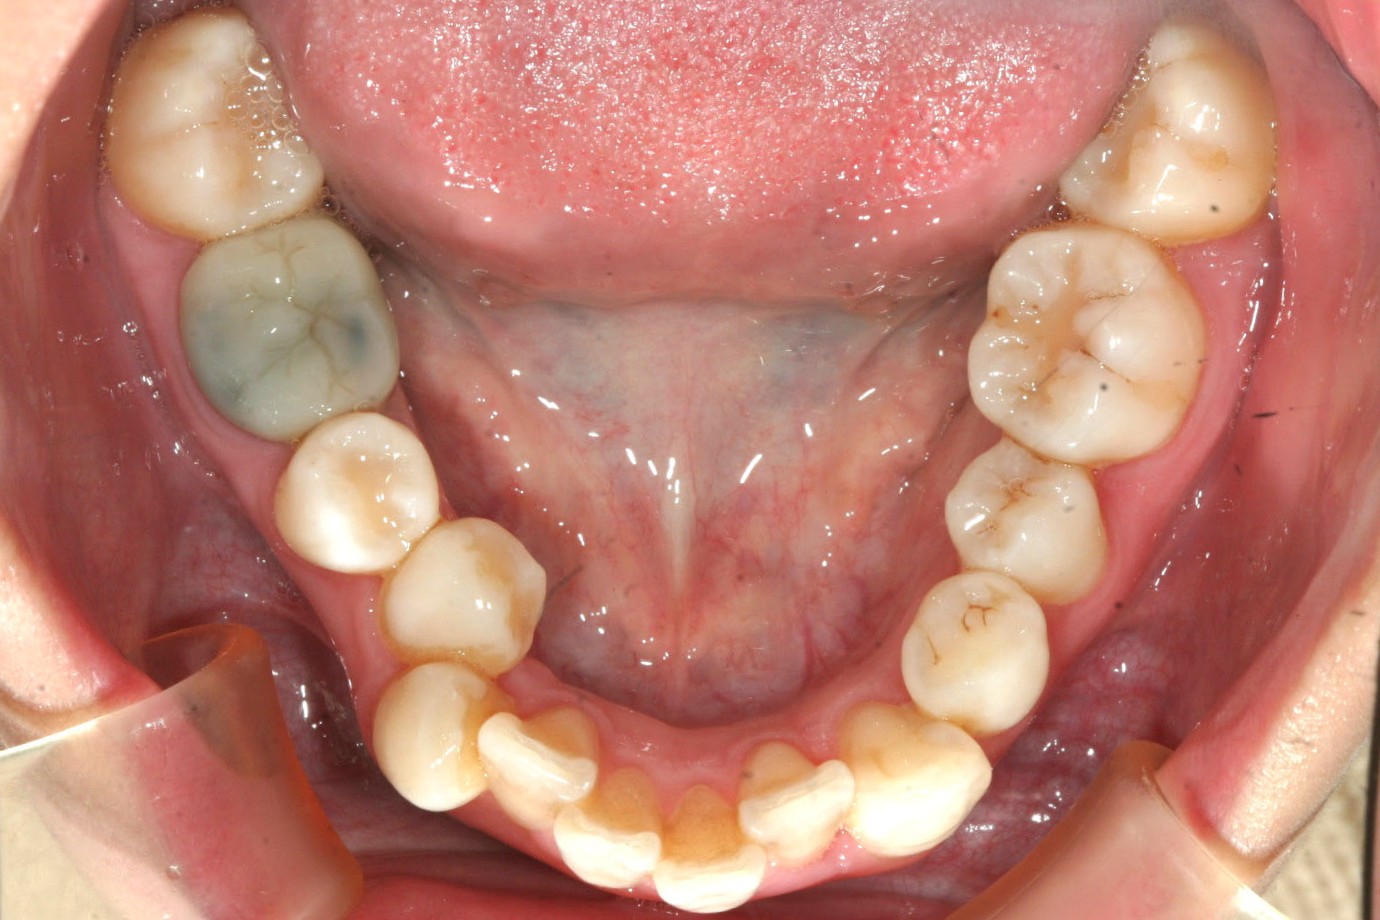

下顎もアーチが狭い為ガタガタが目立ちますね~

下顎はアーチの改善だけでこんなに綺麗になりました。